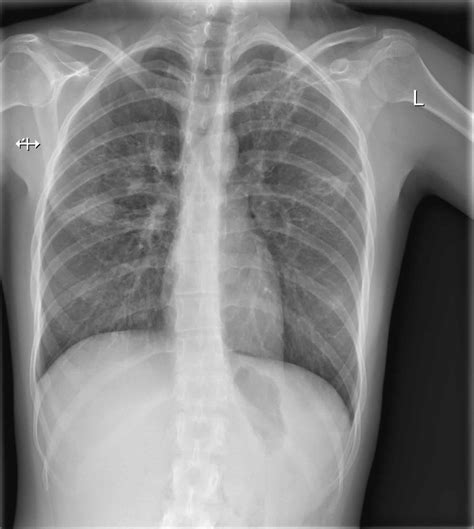

Interpreting Tb X Ray results requires expertise and experience. Radiologists look for specific signs that may indicate TB:

• Cavities: These are hollow spaces in the lungs that can form as the body tries to contain the infection.

• Nodules: Small, round opacities that can be indicative of TB infection.

• Infiltrates: Areas of increased density in the lung tissue, often seen in active TB.

• Pleural Effusion: Fluid accumulation in the pleural space, which can be a complication of TB.

It’s important to note that while Tb X Ray can provide valuable information, it is not always conclusive. Additional tests, such as sputum tests or CT scans, may be required for a definitive diagnosis.